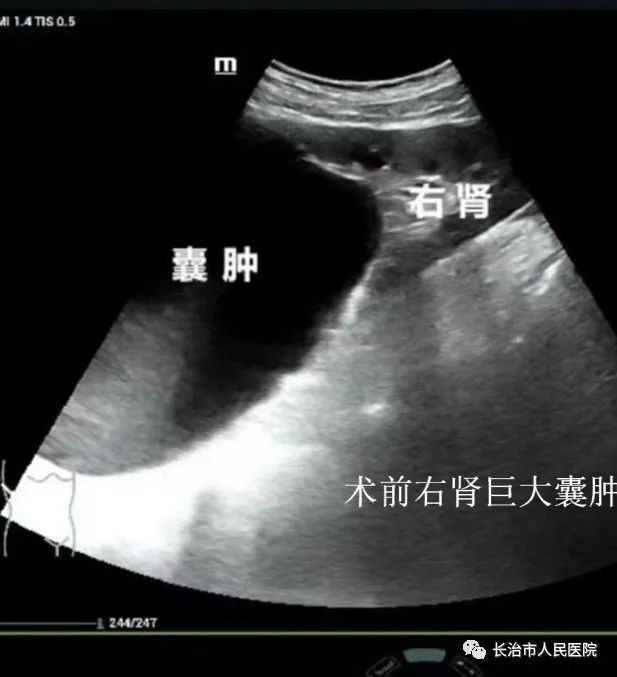

近年来,超声医学技术发展迅猛,尤其是介入超声的发展,迎来了超声从诊断到治疗的里程碑。介入超声以其针过无痕、精准微创等优势获得了临床及患者的认可。10cm大小的肝囊肿,16cm大小的肾囊肿,3cm大小的甲状腺良性结节,0.8cm大小的甲状腺恶性结节,无论其大小良恶,在崔教授精湛的操作技术下,在一根细针的舞动下,在“超声造影”等超声利器的助攻下,短短几分钟或十几分钟,病灶就被“解决”,患者体表只留下一个几乎看不到的针眼。一个巨大肾囊肿患者,术后当场在我院日间手术室门口蹦跳了几下,眉开眼笑,说感觉身体瞬间轻盈了许多。